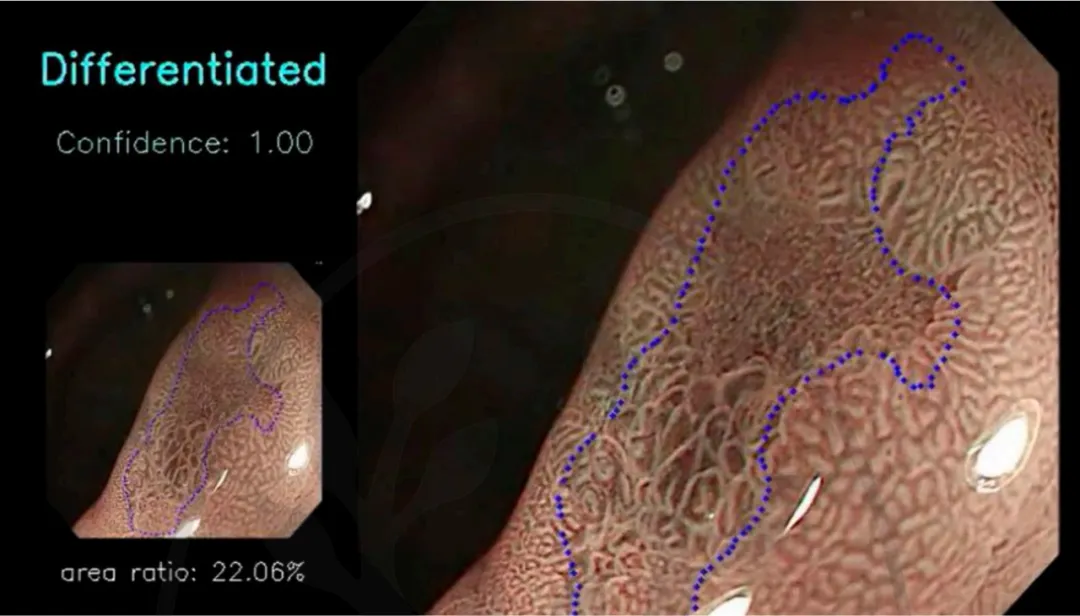

6.3.病理评估:未分化型早期胃癌EGC)的恶性程度以及淋巴结转移的发生率均显著高于分化型EGC。AI可以协助判断病变的分化类型,这在决定手术方案及预后评估中起到关键性作用。